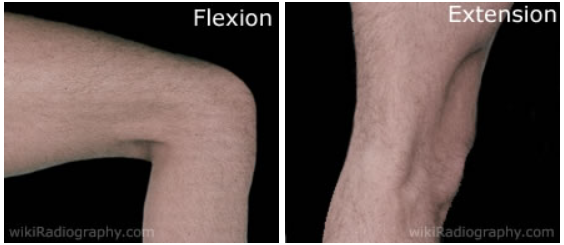

| [Anatomy] Knee(무릎) (0) | 2024.01.12 |